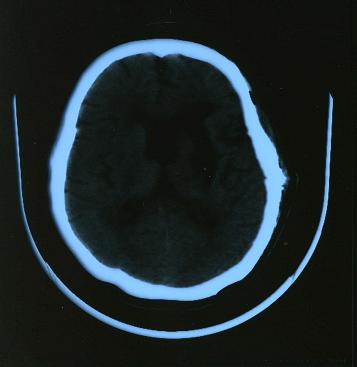

平成15年2

月5日の写真

手術後の写真です。

ほとんどの出血した血は摘出して頂きました。

写真右側の頭蓋骨が取り外してあるのが良く判ります。